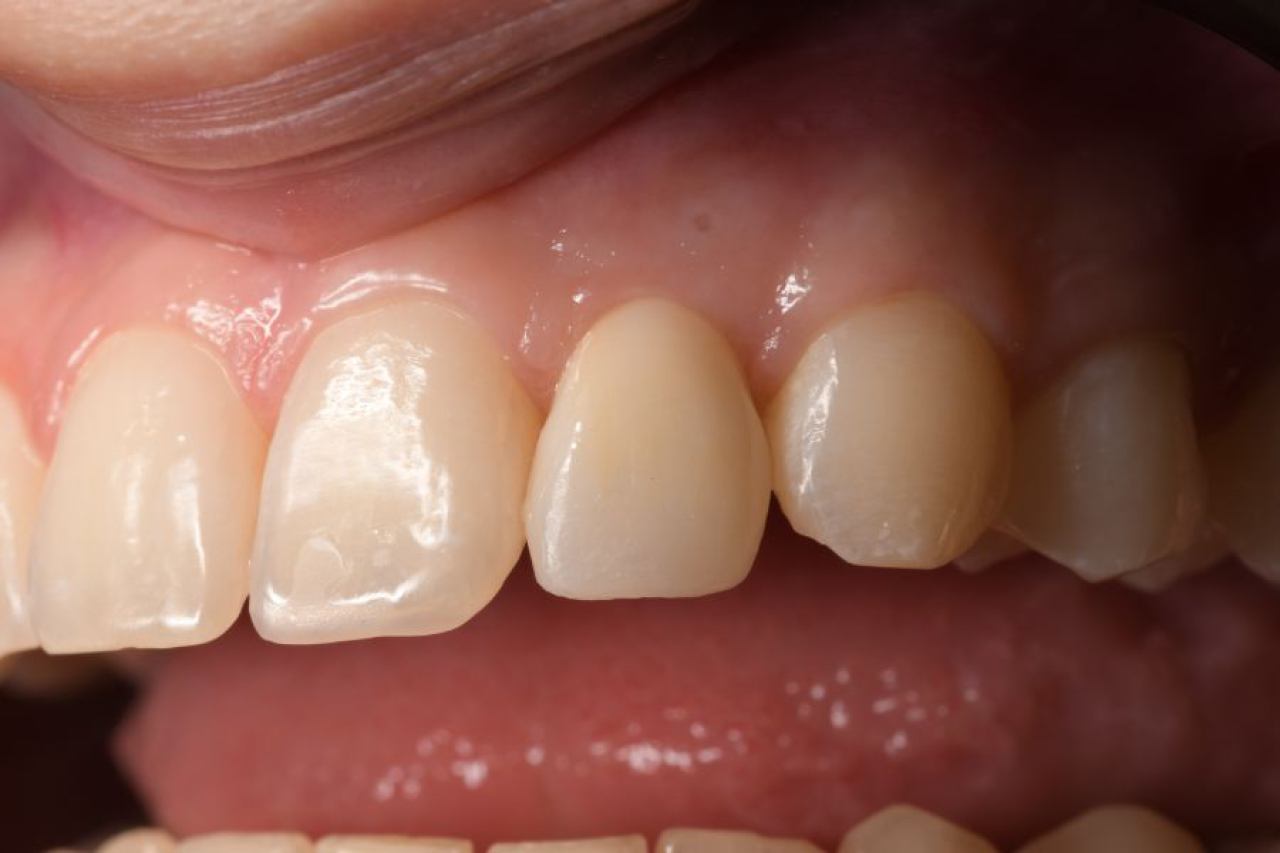

Protetika - mostovi i krunice

Dentalna protetika uključuje fiksne i mobilne radove kojima se nadoknađuje djelomična ili potpuna bezubost. Njihov cilj je povratiti funkciju žvačnog sustava i u konačnici, vrhunsku estetiku.

Marković Dental Clinic u svojoj ponudi ima metalkeramičke radove, potpunokeramičke radove, te u narodu zvane „bezmetalne", odnosno zirkonske radove.